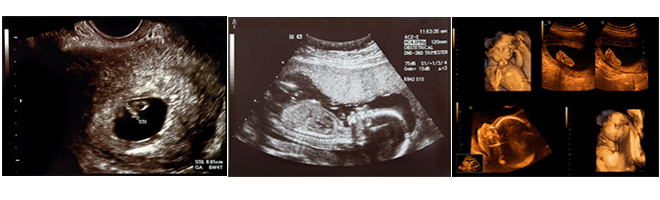

Early pregnancy scan

Week 5: The pregnancy sac is visible.

Weeks 6–7: The embryo can be seen and the heart movement is visible.

Week 8: Early foetal movements and twins can be confirmed.

Weeks 9–10: The outline of the placenta is visible and the first measurements of the foetus can be made to establish a due date.

Midway scanning

Weeks 16–26: The foetus is larger and the organs become visible. The baby’s head is measured and femur length determined – both are important for determining the age of the foetus. Other important structures looked for in a routine scan include the stomach, the bladder, the spine and the external genitalia. The placenta is easily recognised from the rest of the uterus. The amount of amniotic fluid can also be assessed.

A scan done between 18–24 weeks is the single most important routine scan, because it gives an accurate assessment of the gestational age and can detect most of the major abnormalities.